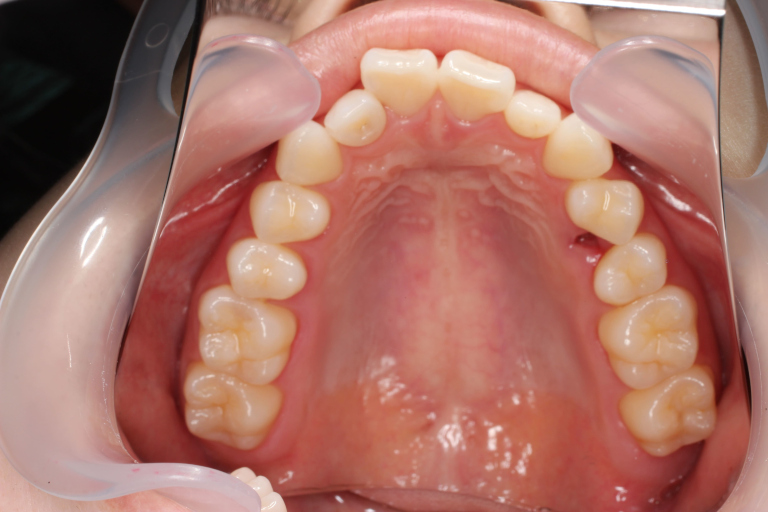

Before

After

| 主訴 | 歯並びの乱れ(叢生)があり、口元の突出感を抑えたい |

| 治療内容 | インビザラインを用いた治療 (非抜歯ケース) |

| 治療期間 | 1年7ヶ月 |

| 治療費用 | 基本料金:660,000円 調整料:3,300円 × 24回 |

| リスク | 取り外し式装置で、1日24時間中22時間使用しなければならず、しっかりと装置を装着できないと歯は思ったように動きません。 |